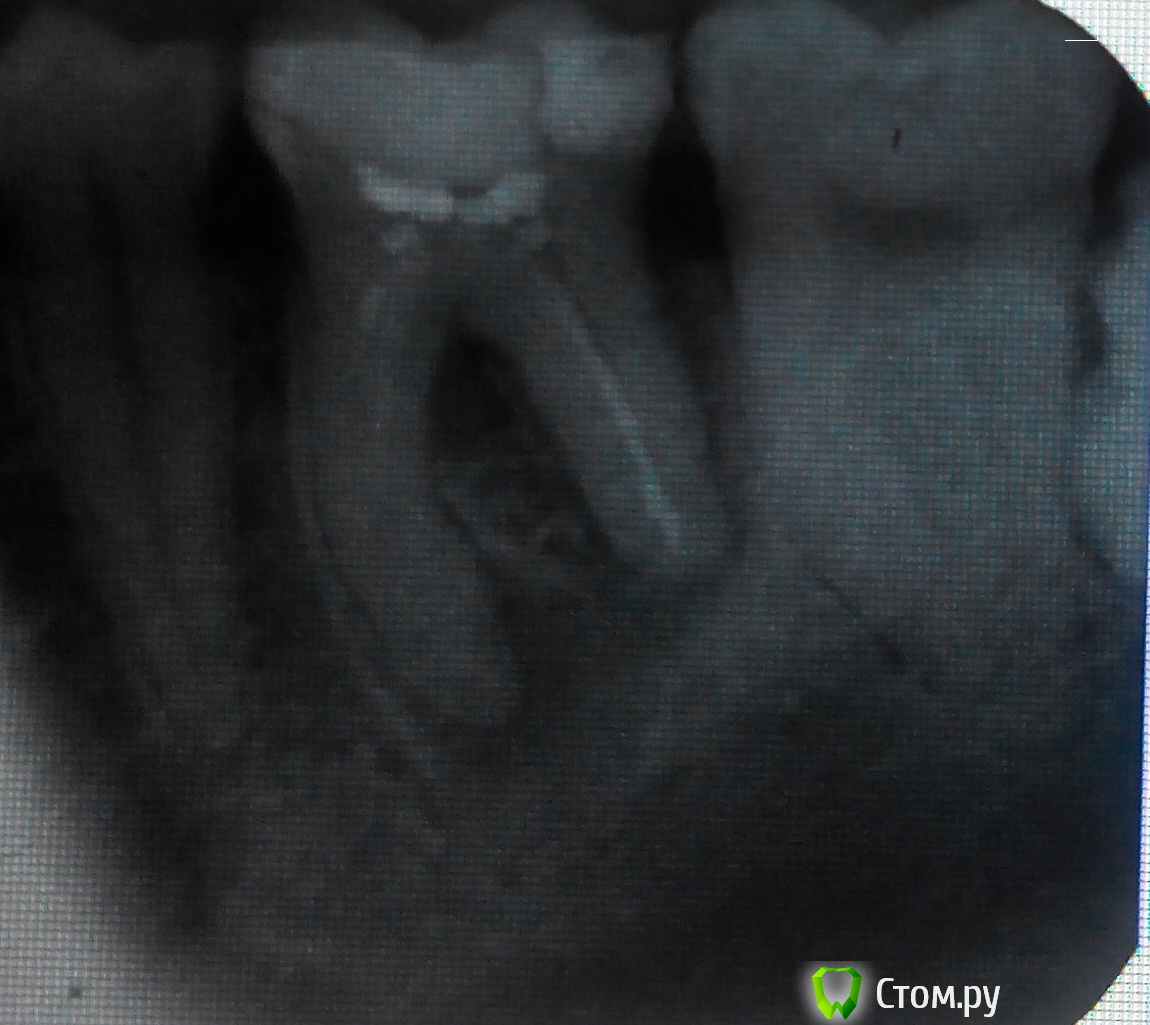

PavelGo Опубликовано 11 февраля, 2014 Поделиться Опубликовано 11 февраля, 2014 Почти уверен, что удалять?Хочется удостовериться, потому что СД 1 типа и импланты не ставят. Ссылка на комментарий

Мартовский Опубликовано 11 февраля, 2014 Поделиться Опубликовано 11 февраля, 2014 Снимок плохой, может и можно полечить, может и нет. Сходите в клинику, где читают компьютерную томограмму, узнаете точно. Ссылка на комментарий